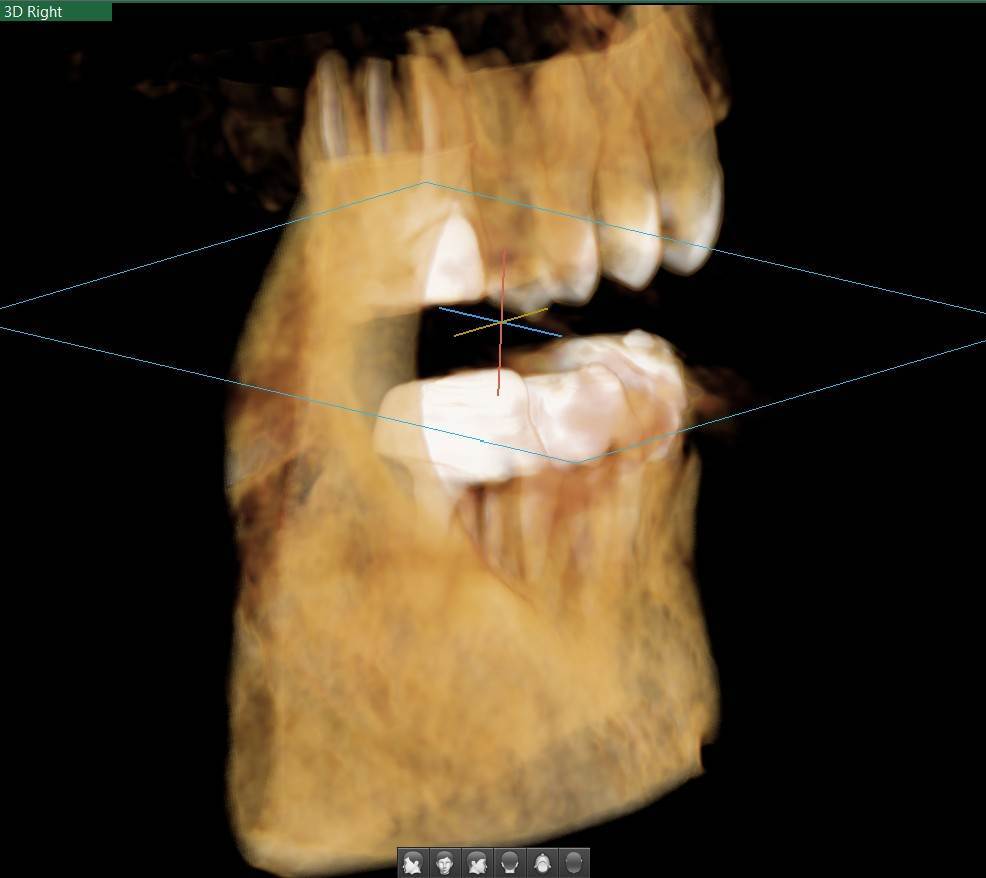

A-V-S Опубликовано 3 марта Поделиться Опубликовано 3 марта Здравствуйте. У меня такая ситуация: В начале января 2026 начал болеть зуб 7ка снизу слева - боль развивалась постепенно - в итоге стало больно жевать. Сделал КТ. Лечащий стоматолог сказал, что это проснулось спящее воспаление, перелечивать каналы зуба сложно - надо сверлить буром и доставать стекловолоконный штифт - надо удалять. В следующие дни открылся свищ и боль ушла. Свищ продолжает быть с периодическим набуханием и сдуванием после выброса гноя белого цвета. Этот зуб лечили с установкой стекловолоконного штифта чуть больше 5 лет назад. Посмотрите, пожалуйста, приложенные снимки и посоветуйте как быть - можно ли перелечить и сохранить зуб ? Ссылка на комментарий

АнтонТЛТ Опубликовано 3 марта Поделиться Опубликовано 3 марта Добрый вечер, лучше выложить несколько срезов этого зуба, либо архив с кт. По представленным снимкам, есть подозрение о наличии трещины между корнями зуба. 1 1 Ссылка на комментарий

Гарриевич Опубликовано 6 марта Поделиться Опубликовано 6 марта Не знаю обрадует Вас это или огорчит, но зуб можно сохранить соседний тоже с воспалением кстати 1 1 Ссылка на комментарий

red_butler Опубликовано 9 марта Поделиться Опубликовано 9 марта В 03.03.2026 в 22:49, A-V-S сказал: можно ли перелечить и сохранить зуб ? можно Ссылка на комментарий